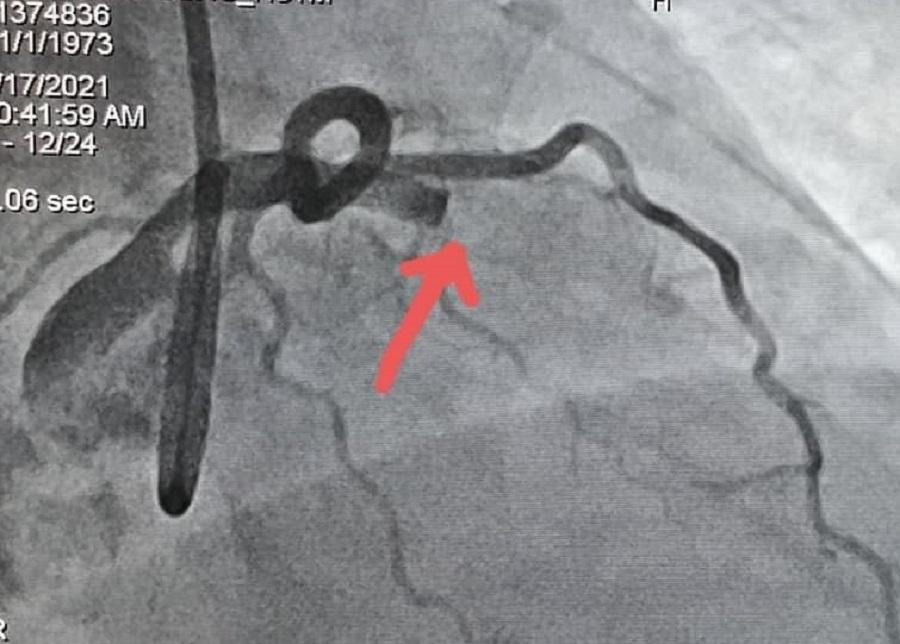

Bệnh nhân được chuyển xuống phòng thông tim can thiệp chụp mạch vành. Hình ảnh kiểm tra ghi nhận người bệnh bị tắc hoàn toàn nhánh động mạch vành liên thất trước bên trái (nhánh động mạch vành lớn nhất tim). Ngay sau đó, bệnh nhân nhanh chóng rơi vào tình trạng huyết áp tụt rất thấp, ngưng tim. Ê kíp bác sĩ và điều dưỡng bất chấp rủi ro lây nhiễm, nỗ lực hồi sức tim phổi cho bệnh nhân ngay trong phòng thông tim.

| Hình ảnh động mạch vành của bệnh nhân trước và sau khi được thông tim đặt stent |